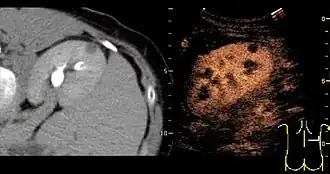

Contrast-enhanced renal ultrasonograph, showing a renal cell carcinoma successfully treated with thermal ablation, as no contrast enhancement is seen[1]

Unspecific cortical lesion on CT is confirmed cystic and benign with contrast-enhanced renal ultrasonography using image fusion.[1]